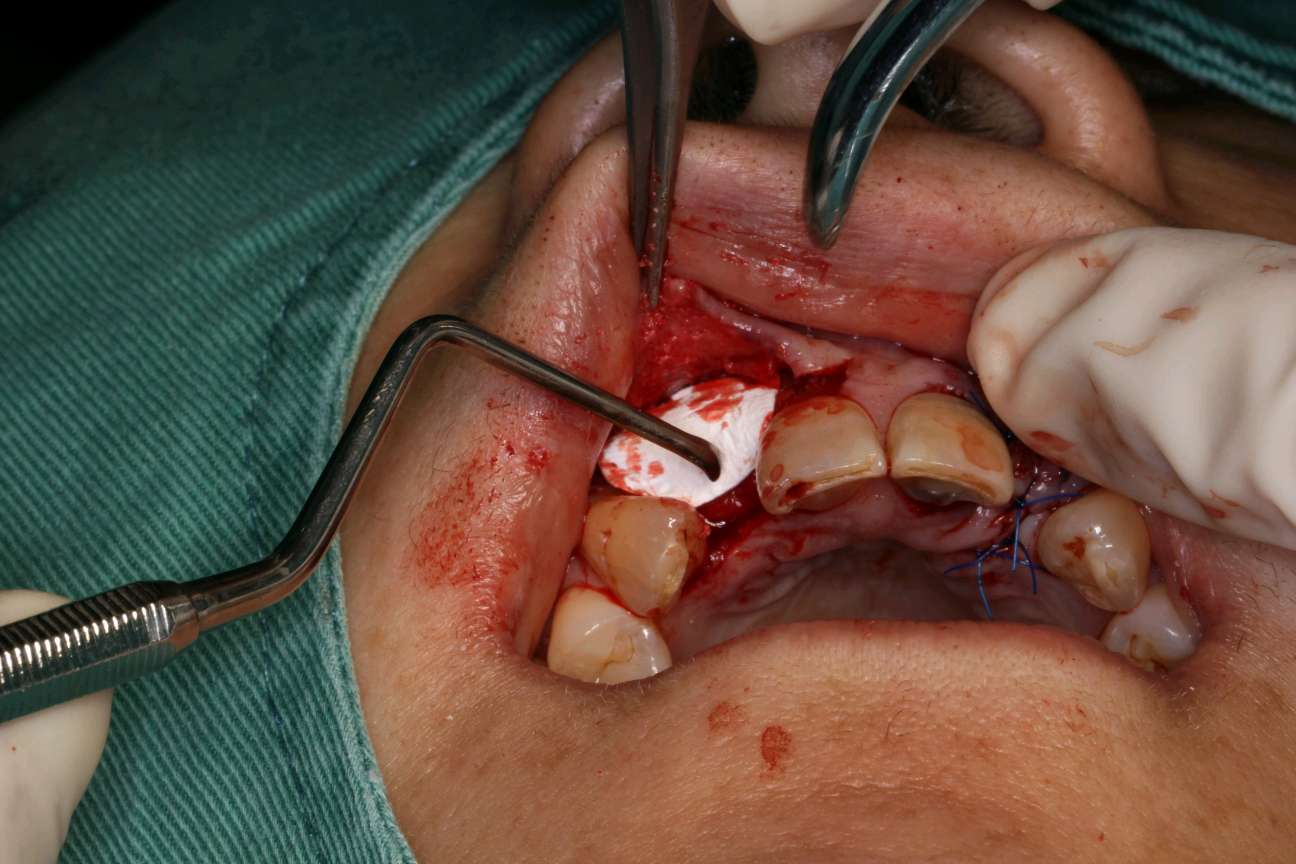

术中